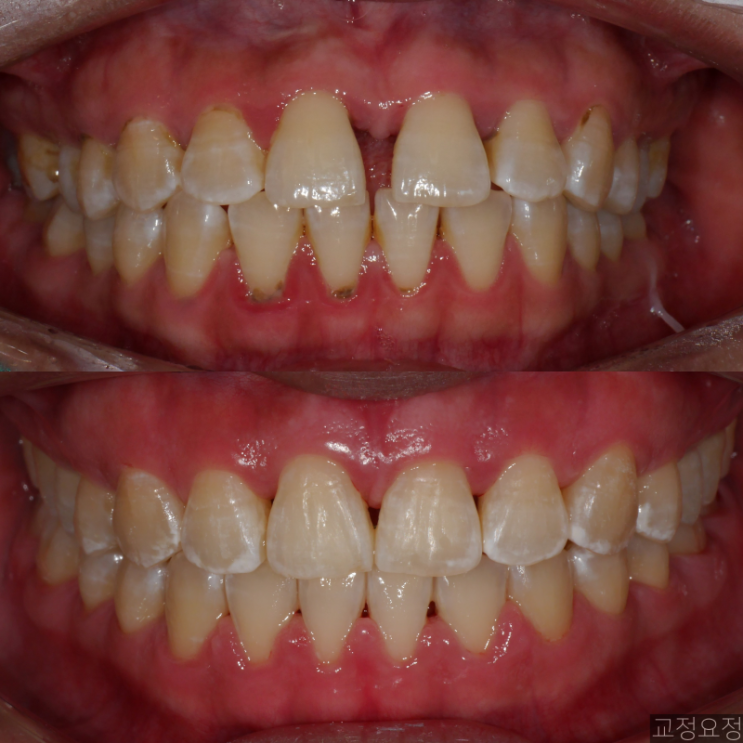

?삐뚤빼뚤한 송곳니 덧니 치아교정 케이스 / 악궁확장 없이 비발치 케이스 - 전후사진, 치료기간, 주의사항

안녕하세요 ! 치과의사 교정요정 입니다. 오늘은 삐뚤빼뚤한 치아를 발치하지 않고 교정한 간단한 케이스 ...